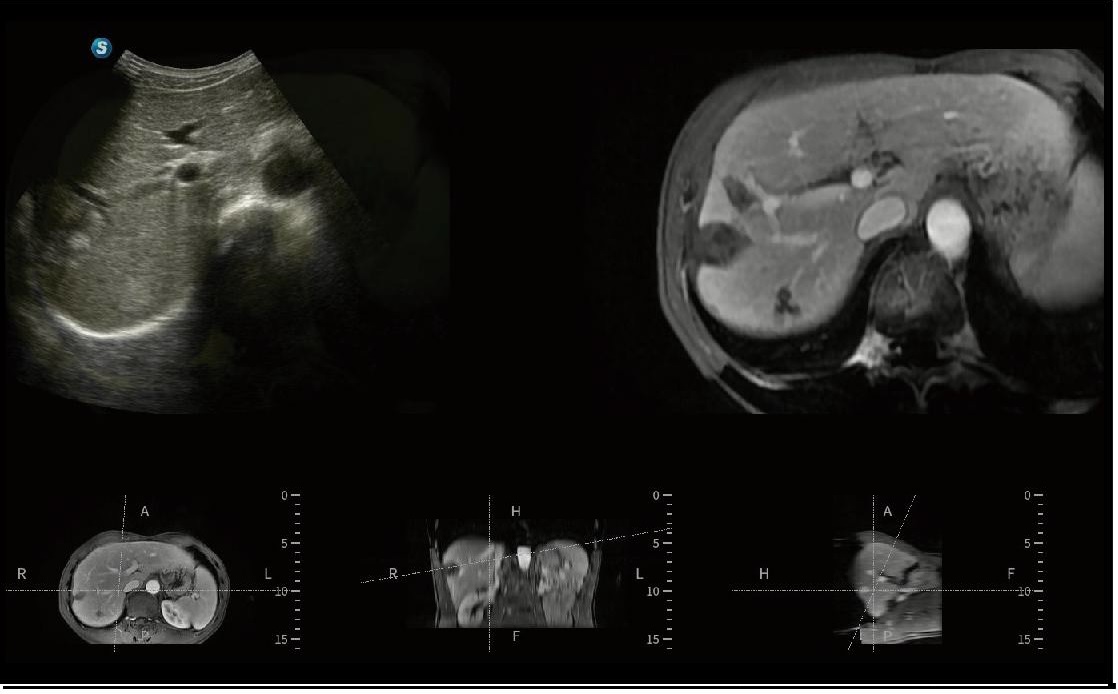

SONO FUSION

Prob içerisine entegre edilmiş manyetik sensör sayesinde, SonoFusion harici bir manyetik sensör ihtiyacını ortadan kaldırır ve ultrason verilerini BT/MR verileriyle birleştirerek görüntü eşleştirme yoluyla eşzamanlı gösterim sağlar. Bu entegrasyon, klinisyenlerin hastalıkları kapsamlı bir şekilde analiz etmesini kolaylaştırır.